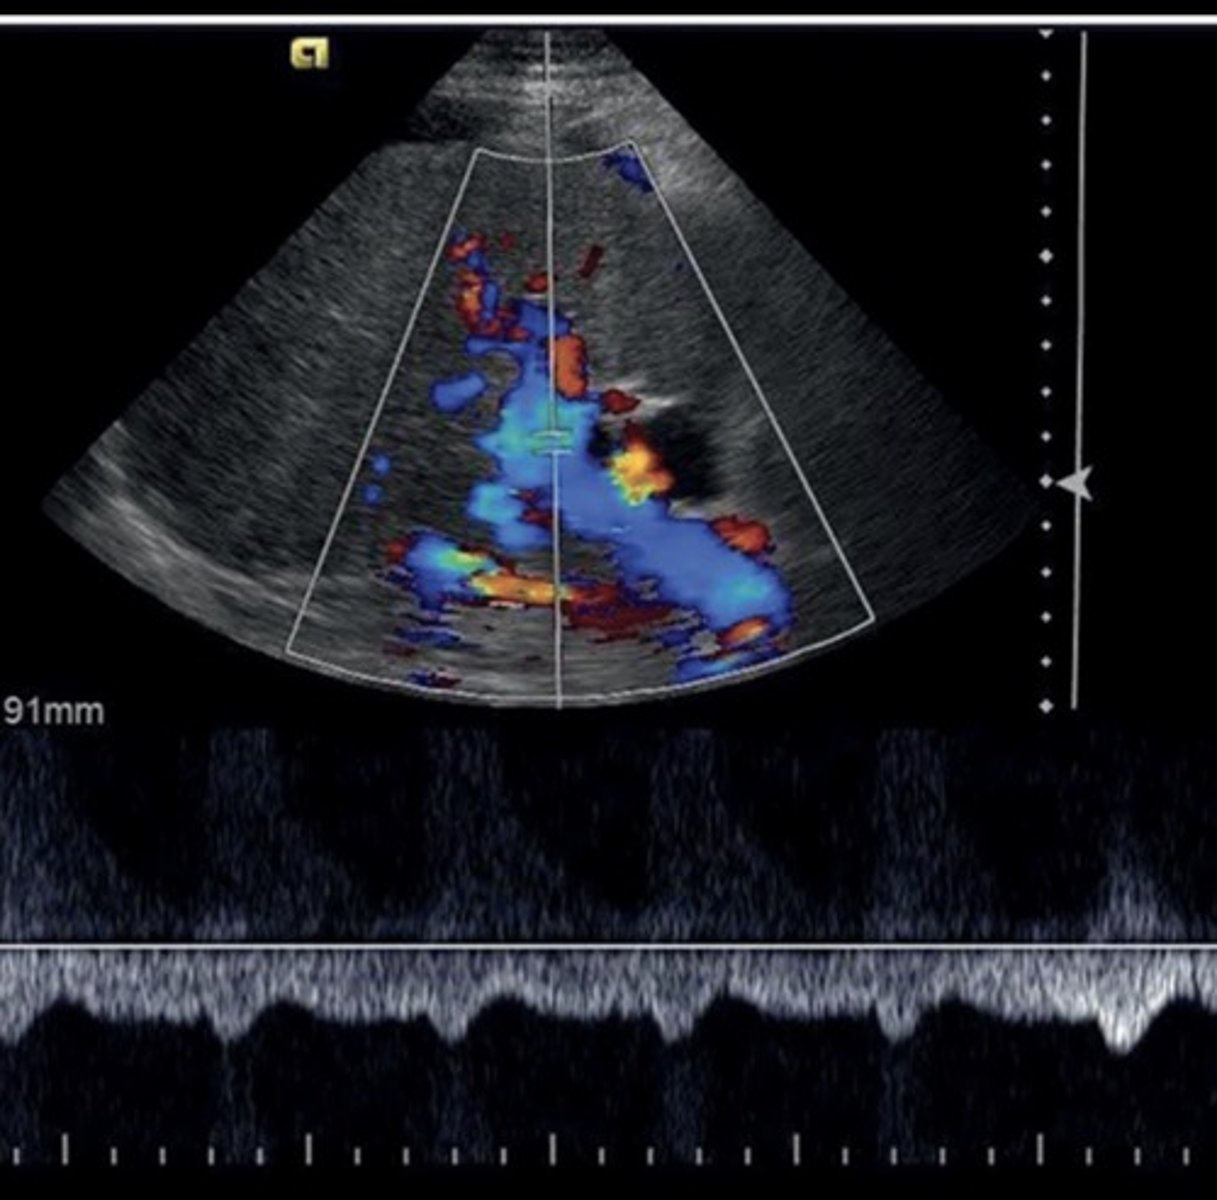

Main Portal Vein Doppler Waveform

Monophasic continuous waveform

Hepatopetal flow (antegrade flow)

Hepatic Vein Doppler Waveform

Triphasic

Antegrade & retrograde flow - cardiac pressure changes

Hepatic Vein Doppler

S wave: ventricular systole

D wave: atrial filling

A wave: atrial contraction

Inspiration depresses systolic wave

Exhalation augments systolic wave

Valsalva diminishes pulsatility